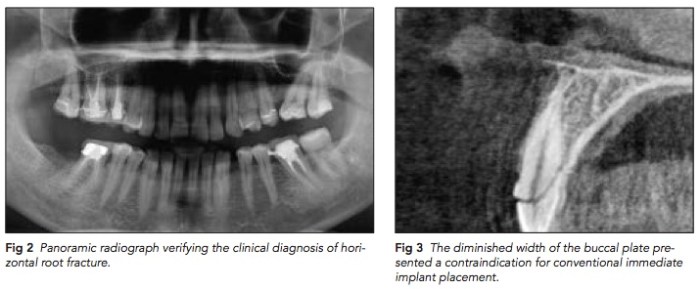

我記得之前有念過跟這篇很類似的文章, 就是如果你確定斷根的牙齒是乾淨的, 你就可以直接將這斷根的狀況當成自然的骨質, 就直接種進去就好. 只是我當初念的文章是後牙, 那時的理由是因為想要做immediate implantation. 這篇文章更厲害了, 為了將上顎前牙的buccal plate保住, 決定將水平斷根的右上正中門牙先留住, 直接鑽洞, 然後拿除其他三個面的斷根,只留buccal side的斷根. 因為這樣的治療方式沒有長期的追蹤也沒有什麼研究的理論基礎, 希望未來能有更多相關的文章作為參考.